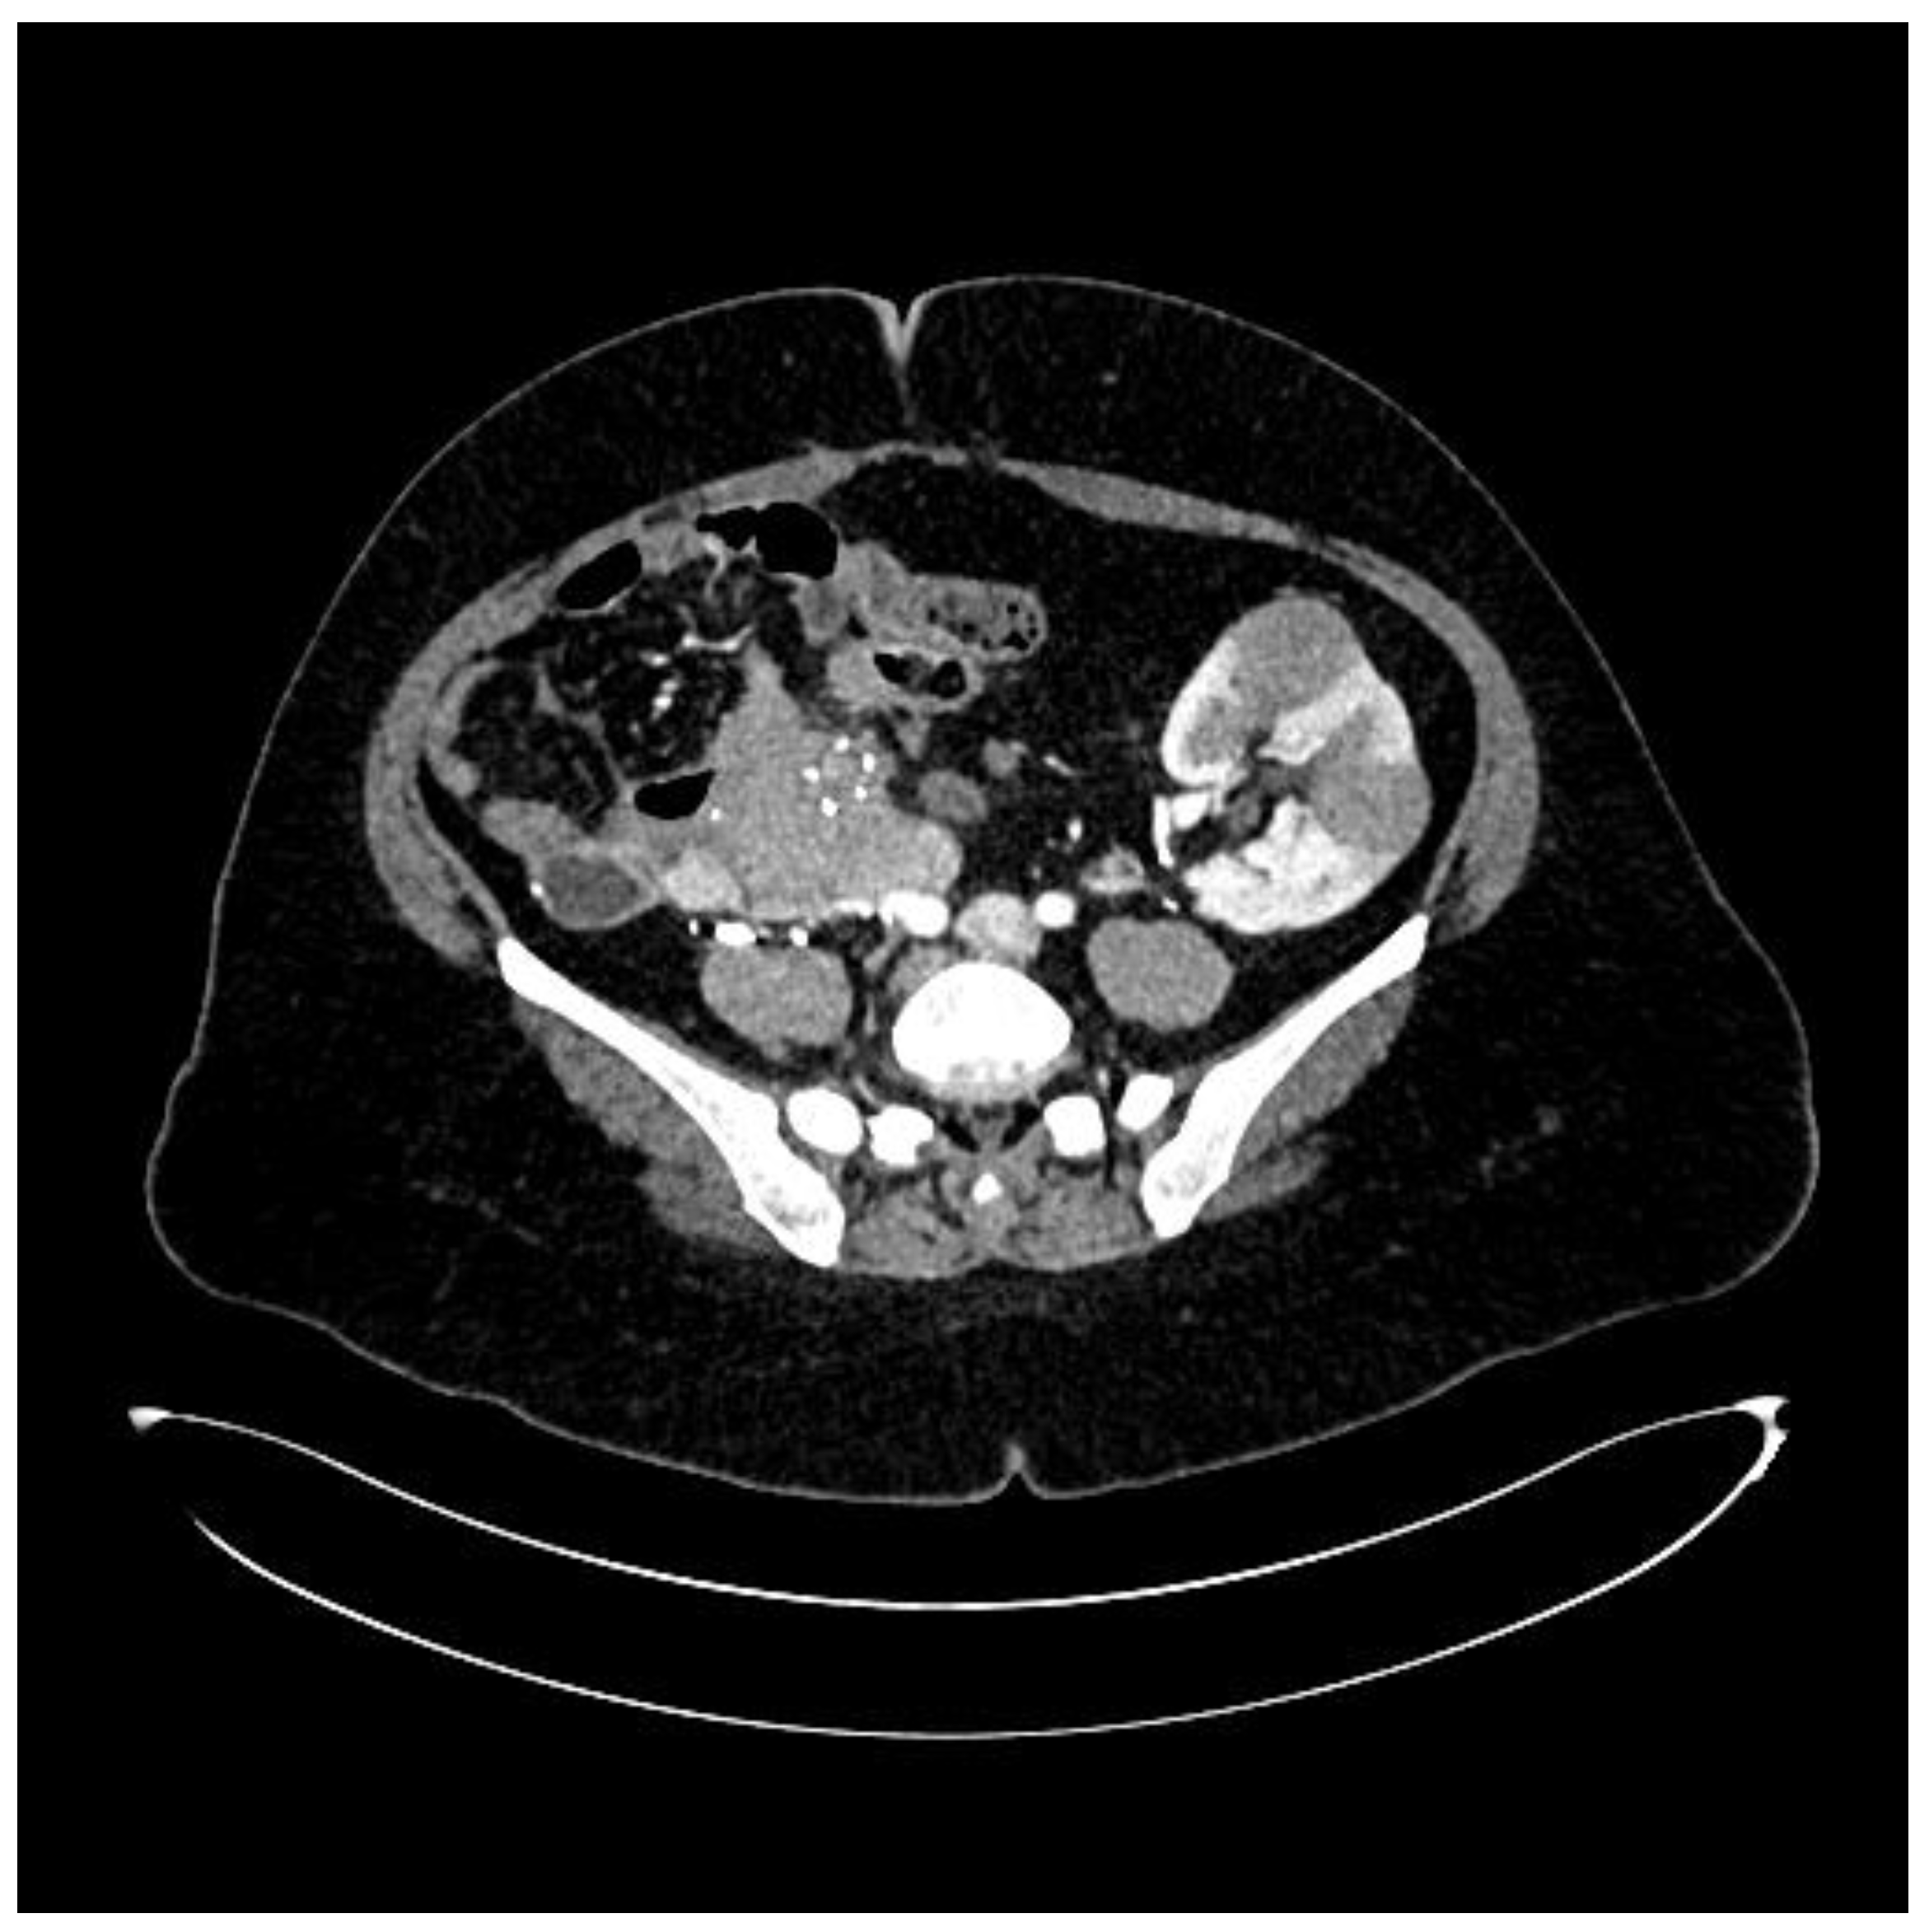

During hospitalization, an ultrasound of the transplant kidney was preformed and after the registered three infiltrative circular lesions isoechoic with parenchyma, a CT scan was also performed using CT-GE Medical Systems, LCC, Revolution HD, Belgrade, Serbia, revealing three lesions in the transplanted kidney, a larger lesion in the body of the pancreas, and additional lesions in the native kidneys (Figure 1, Figure 2 and Figure 3). Additionally, a lesion was identified in the medial lobe of the right lung adjacent to the sixth rib cartilage.

Figure 2. CT scan image: post-transplant lymphoma in a kidney-pancreas transplant.